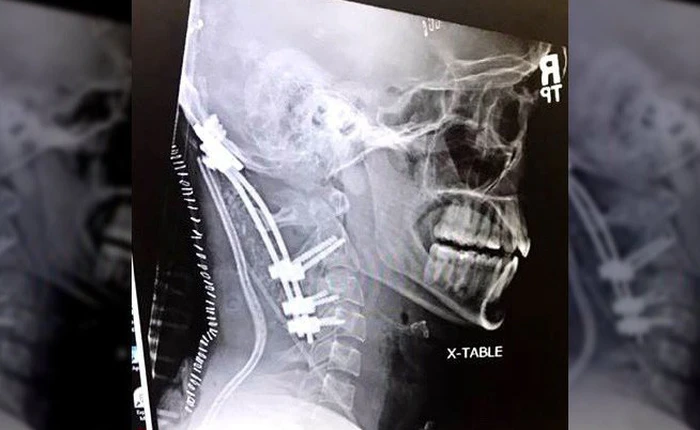

tai nạn kinh hoàng